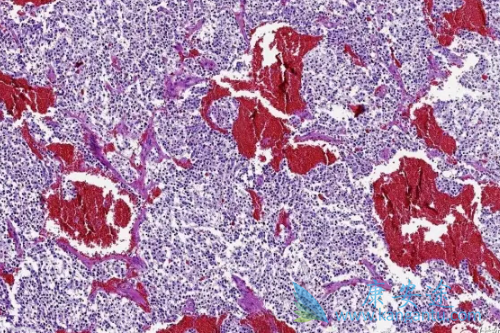

嗜铬细胞瘤和副神经节瘤都属于神经内分泌肿瘤,比较罕见,但是由于这类肿瘤没有典型的遗传组织学、分子标记物等特异诊断物质,诊断困难,因此往往待肿瘤发生转移时才被发现。不过在今年的AACE大会上,刚结束的II期试验结果表明:对于无法采用手术切除方式治疗的恶性嗜铬细胞瘤、副神经节瘤,酪氨酸激酶抑制剂卡博替尼(Cabozantinib)可能有用武之地。

该研究纳入了14例患者,7例患者存在嗜铬细胞瘤、7例患者有副神经节瘤,其中10例患者有可检测观察的转移病灶,除了仅局限于骨骼转移的患者之外,还有淋巴结、肝脏和肺部等处的转移。卡博替尼(Cabozantinib)初始剂量为60mg/天,根据患者耐受情况减少至20或40mg/天。根据实体肿瘤疗效评估标准(RECIST)。

10例有可观测病灶的患者中除1例外均获得部分或中等疗效,中位无进展生存期为12.1个月,范围为0.9-37个月,而接受卡博替尼(Cabozantinib)前中位无进展生存期为5个月(范围为0.9-8个月)。在这些患者中出现比如手足综合征、味觉障碍、黏膜炎、疲劳、体重减轻、高血压和腹泻(1级或2级不良反应)等,有一例出现胰腺酶升高和直肠瘘(3级不良反应),没有观测到4级或5级不良事件发生。